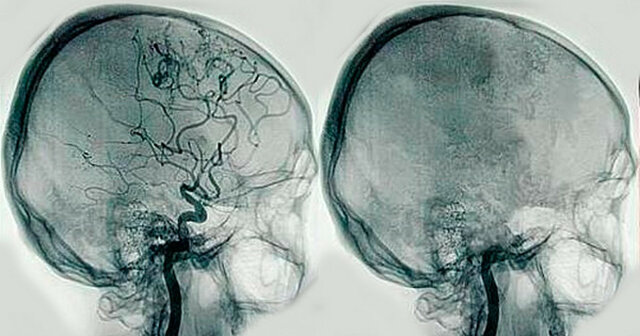

• António Egas Moniz

António Egas Moniz

Inventó la Angiografía, técnica mediante la cual se puede apreciar con precisión el estado de las arterias. Dedicó la mayor parte de su vida al estudio del desarrollo de terapias para enfermedades mentales como la esquizofrenia. (Buzzi, A. E. 2010).